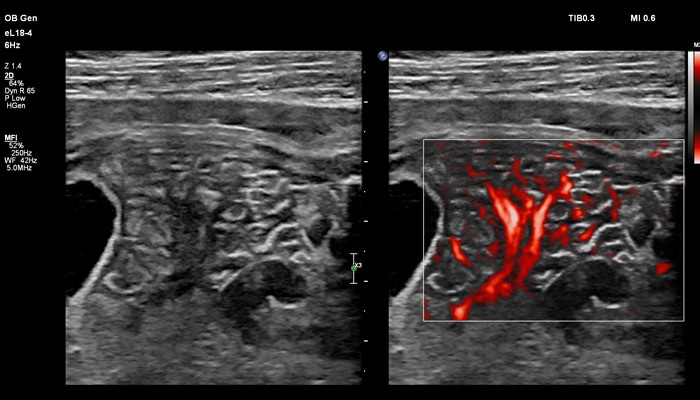

Точная оценка состояния плаценты важна при определении сроков родоразрешения, а также при планировании хирургических вмешательств. Изображения показывают нормальный миометрий и четкую границу с плацентой. С визуализацией микрокровотока (MFI) хорошо представлены дугообразные артерии матери, спиральные артерии, а также ветвящиеся ворсинчатые артерии, что подтверждает нормально развитую сосудистую систему.

Клинические исследования, проведенные экспертами детской больницы штата Аризона (США) во главе с Д-ром Льюсом Гонкалвсом с целью определения наличия нормальной сосудистой структуры плаценты при подозрении на ее патологию, показали, что инновационная технология сверхширокополосной PureWave матрицы датчика eL18-4 способна изменить привычный способ, которым врачи интерпретируют нормальный и аномальный сосудистый поток в плаценте.